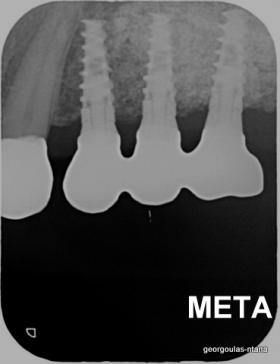

ΑΝΟΙΚΤΗ ΑΝΥΨΩΣΗ ΙΓΜΟΡΕΙΟΥ Κ ΤΟΠΟΘΕΤΗΣΗ 3 ΕΜΦΥΤΕΥΜΑΤΩΝ

Στην ασθενή αυτή πραγματοποιήθηκε ανοικτή ανύψωση ιγμορείου άνω αριστερά. Σε πρώτη φάση πραγματοποιήθηκε η οστική αύξηση και 6 μήνες μετά τοποθετήθηκαν 3 εμφυτεύματα. Τόσο στην πανοραμική όσο και στην τομογραφία κωνικής δέσμης (CBCT) που πραγματοποιήθηκαν 6 μήνες μετά την ανύψωση είναι εμφανής ο σχηματισμός οστού. Η τελευταία ακτινογραφία και φωτογραφία λήφθηκαν 5 χρόνια μετά την προσθετική αποκατάσταση.